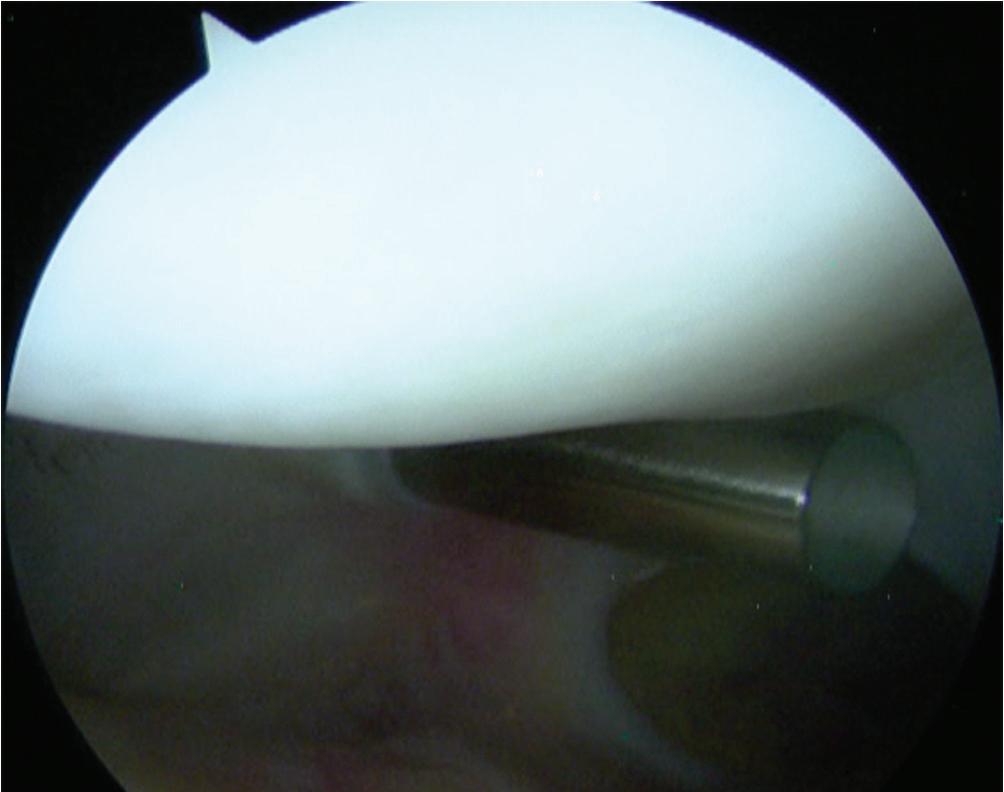

Posterior Compartments (Fig. 1-12)

■ For access to the posteromedial and posterolateral compartments of the knee, the modified Gillquist maneuver is typically performed.

■ For visualization of the posteromedial compartment, the knee is flexed to 90 degrees and a blunt trocar is placed through the AL portal toward the anterolateral wall of the medial femoral condyle.

■ The obturator is slowly advanced posteriorly while the knee is slowly extended until it “pops” through the interval between the medial femoral condyle and the PCL; a valgus stress is applied to help facilitate access.